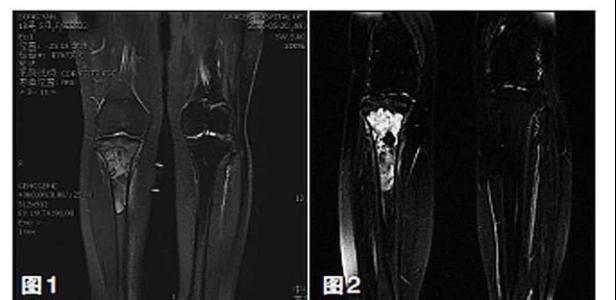

新輔助化療的目的是盡早殺滅遠處微小轉移灶,縮小腫瘤及周圍炎性水腫反應區,以利于后續的保肢手術;觀察腫瘤對化療的敏感性,為進一步指定個體化的術后化療方案奠定基礎。骨肉瘤新輔助化療下的保肢治療如下圖所示: